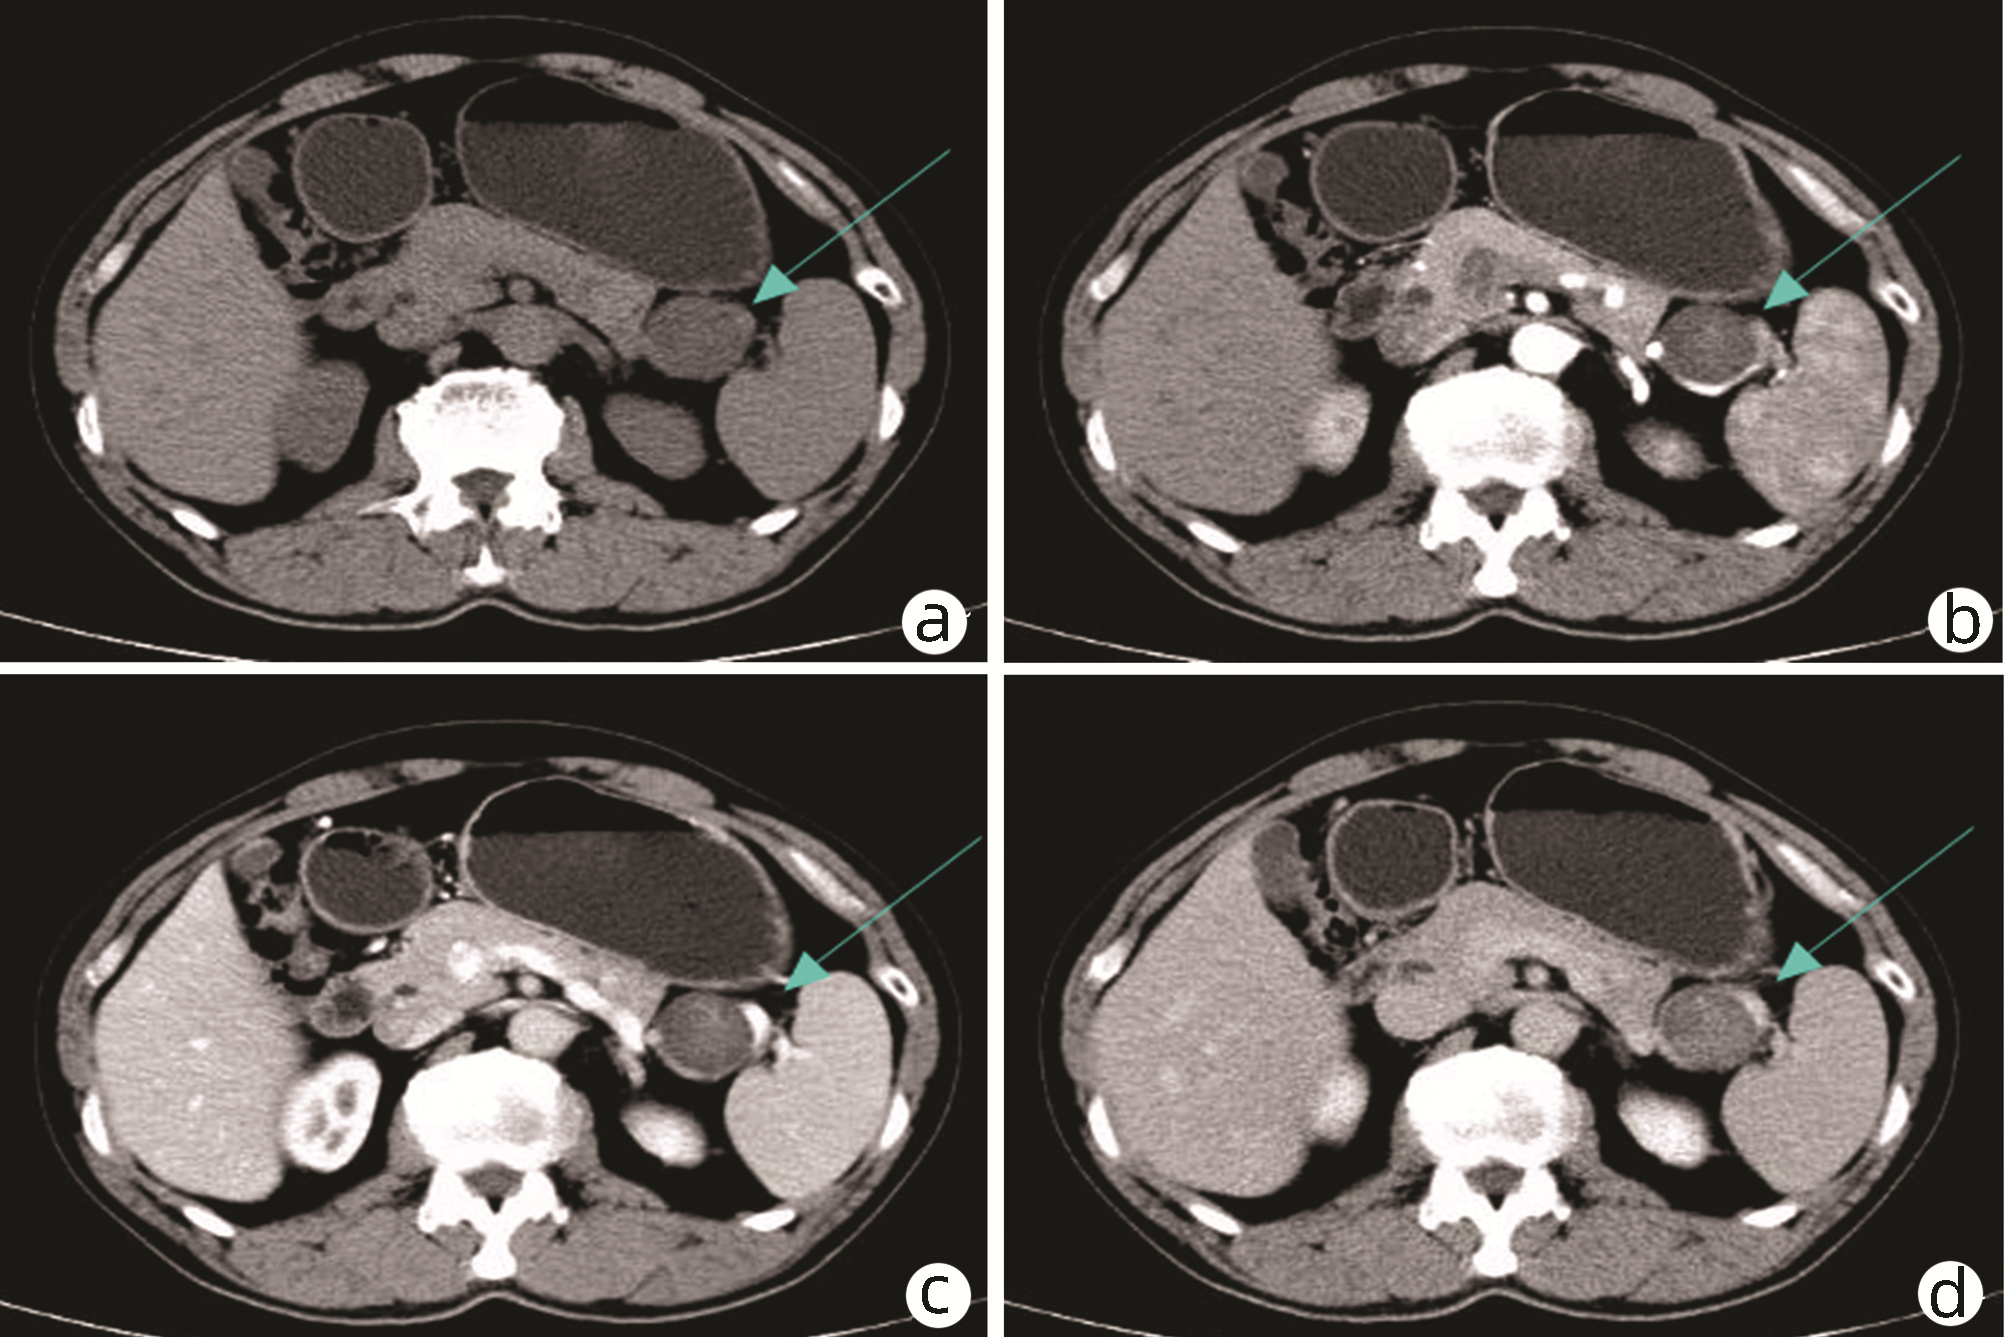

Hepatocellular carcinoma with bile duct tumor thrombus: A case report

Renjie LU, Fangfang SUN, Jie DU, Lirong ZHAO

2022, 38(8): 1872-1874. DOI: 10.3969/j.issn.1001-5256.2022.08.028

Abstract(831) HTML (461) PDF (3665KB)(88)

Abstract: